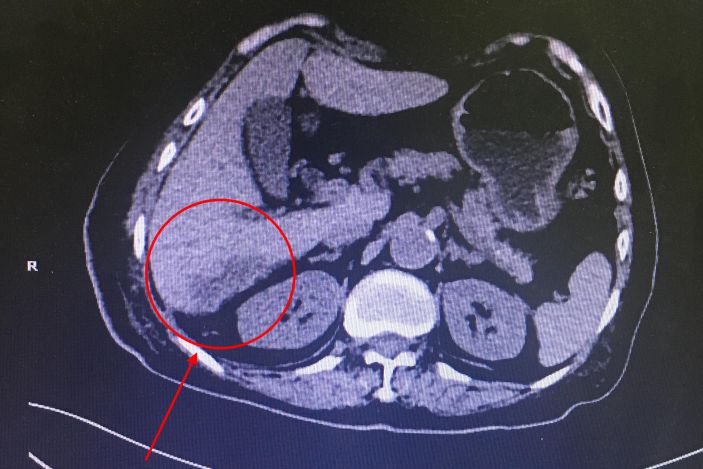

△4月11日CT顯示病竈已經恢複良好

術後第二天許婆婆上腹部疼痛症狀消失,體溫恢複正常,健康狀況逐日好轉。4月11日,CT顯示病竈已經恢複良好,随于當天拔除引流管。4月15日康複出院。